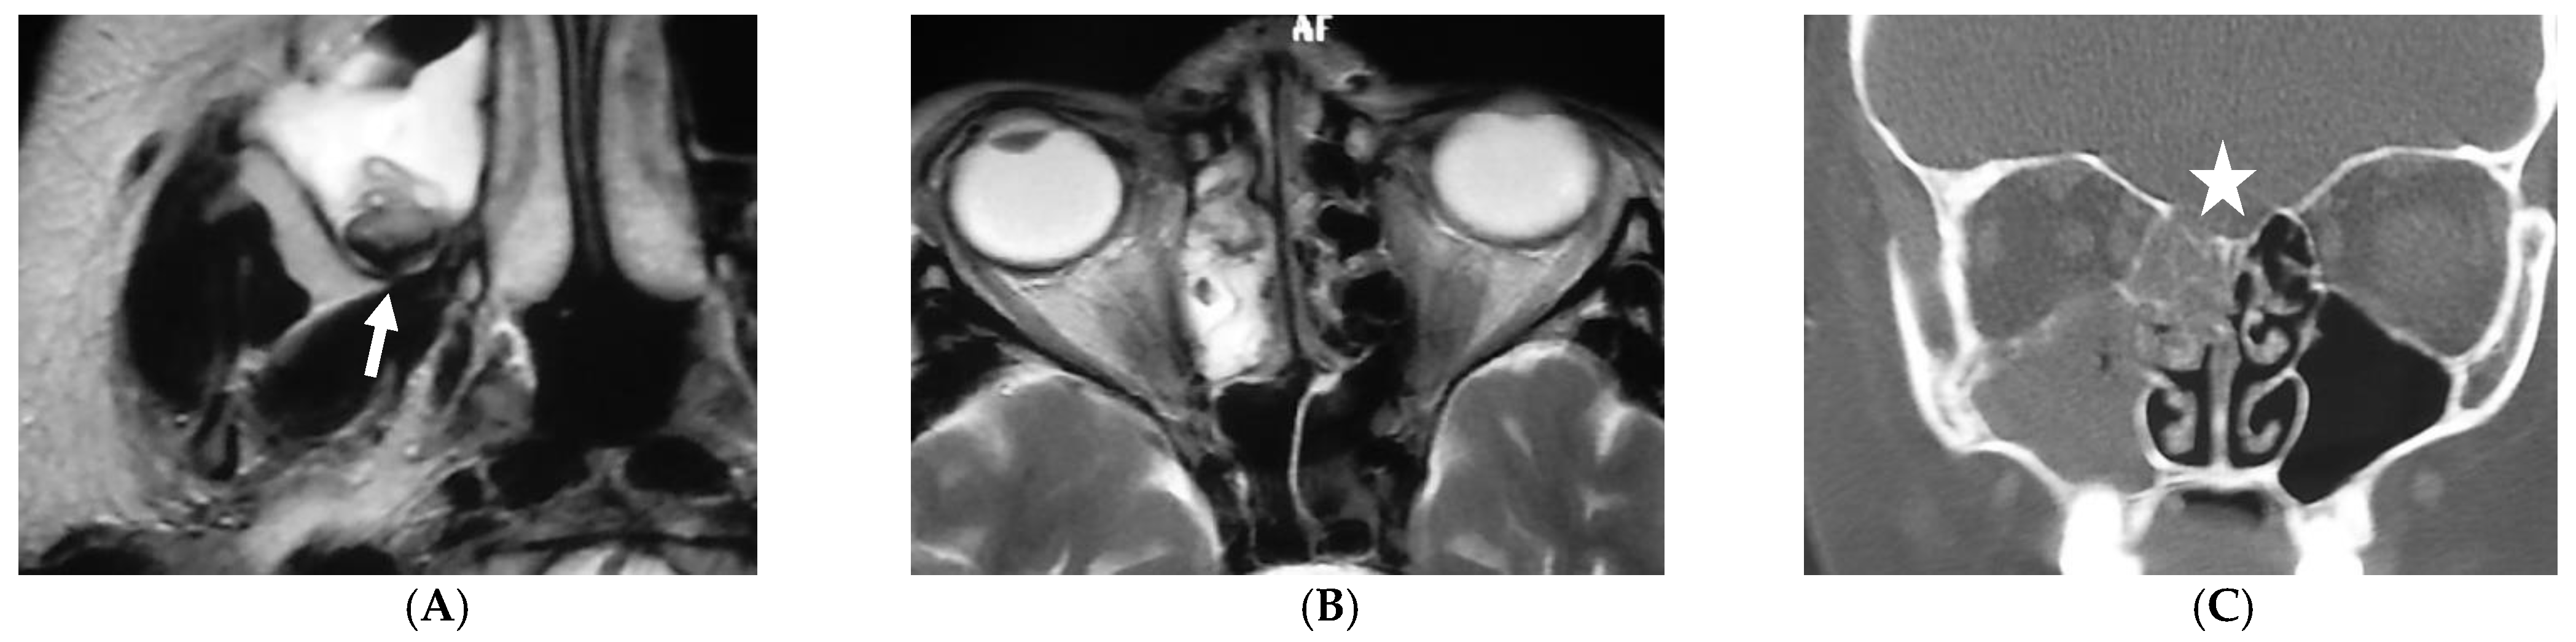

5.1. Fungal Sinus Disease

- Ashdown, B.C.; Tien, R.D.; Felsberg, G.J. Aspergillosis of the brain and paranasal sinuses in immunocompromised patients: CT and MR imaging findings. AJR Am. J. Roentgenol. 1994, 162, 155–159. [Google Scholar] [CrossRef]

- Aribandi, M.; McCoy, V.A.; Bazan, C., 3rd. Imaging features of invasive and noninvasive fungal sinusitis: A review. Radiographics 2007, 27, 1283–1296. [Google Scholar] [CrossRef]

- Middlebrooks, E.H.; Frost, C.J.; De Jesus, R.O.; Massini, T.C.; Schmalfuss, I.M.; Mancuso, A.A. Acute Invasive Fungal Rhinosinusitis: A Comprehensive Update of CT Findings and Design of an Effective Diagnostic Imaging Model. AJNR Am. J. Neuroradiol. 2015, 36, 1529–1535. [Google Scholar] [CrossRef]